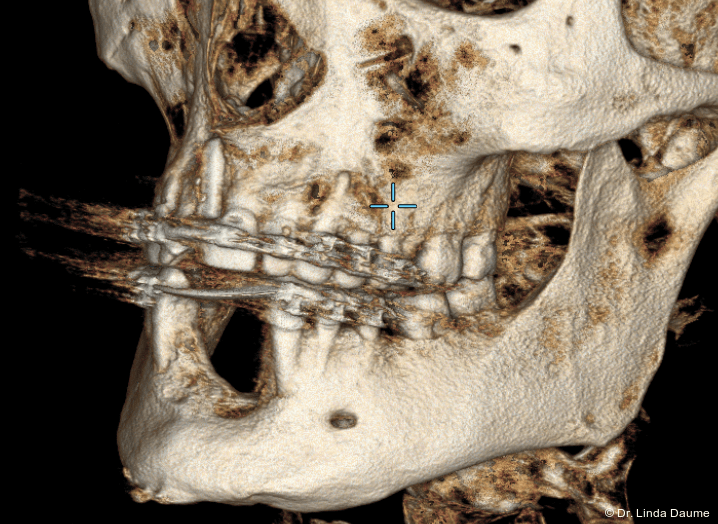

Nach umfassender Aufklärung erfolgte – aufgrund des unzureichenden Knochen- und Weichgewebsangebots für eine unmittelbare Implantation – eine Unterkieferdistraktion zur vertikalen Augmentation des Knochens und zur Vermehrung des Weichgewebes durch eine kontinuierliche Dehnung. In Intubationsnarkose wurde der Knochendefekt dargestellt und das Segment in Regio 32-42 osteotomiert. Das Segment war an der lingualen Schleimhaut gestielt, mobilisiert und gut durchblutet. Anschließend wurde der Distraktor (KLS Martin) angepasst und eingebracht (Abb. 2a–c). Abschließend erfolgten der Wundverschluss und eine postoperative Röntgenkontrolle (Abb. 3).

Nach einer Latenzphase von sieben Tagen begann die Distraktion mit 1 mm pro Tag, aufgeteilt in mehrere Einzelaktivierungen unter engmaschiger Kontrolle. Nach Erreichen der vorgesehenen Endposition begann die Konsolidierungsphase (Abb. 4). Der Distraktor wurde nach acht Monaten entfernt und es erfolgte die Implantation in Regio 32 und 42 mit lokaler Augmentation (Abb. 5a+b). Nach einer weiteren Einheilphase von fünf Monaten wurden die Implantate freigelegt und das Weichgewebe mittels eines freien Schleimhauttransplantats vom Gaumen optimiert. Die prothetische Versorgung konnte anschließend festsitzend mit einer implantatgetragenen Brücke von 32-42 realisiert werden (Abb. 6).